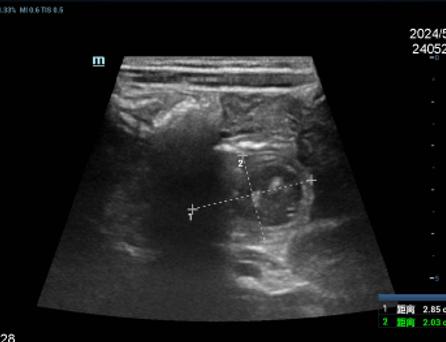

完善影像学检查,考虑存在十二指肠重复畸形可能

2.jpg